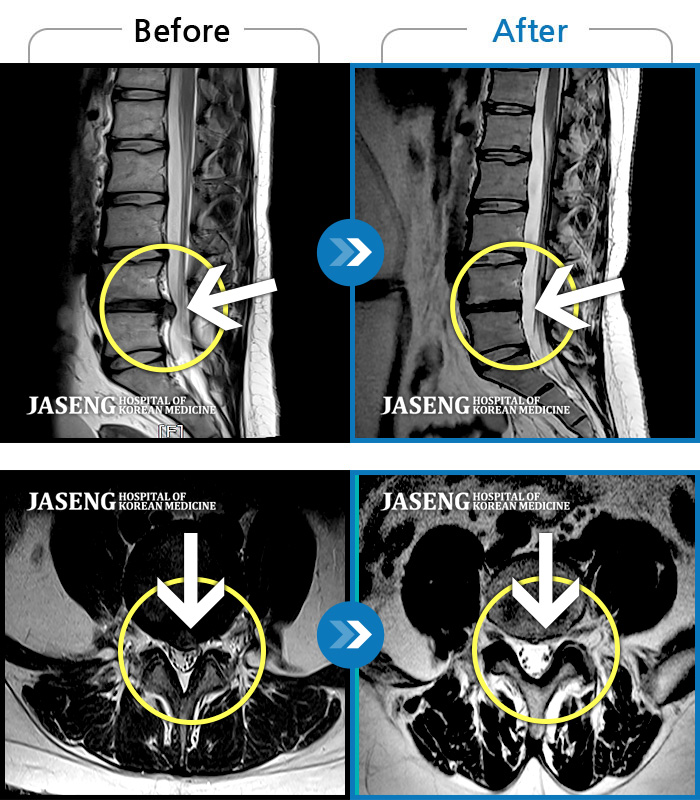

허리디스크

해운대 · 김상돈 원장

허리가 찌릿찌릿하고 찢어질 것 같은 통증

촬영시기

2024.01.08 ~ 2025.08.12

2025.08.29

조회수 271